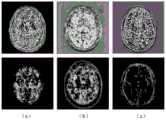

图4为特征增强前后对比图。在图4中,(a)为T1特征图,(b)为T1-IR特征图,(c)为T2-FLAIR特征图。Figure 4 is a comparison diagram before and after feature enhancement. In Figure 4, (a) is the T1 feature map, (b) is the T1-IR feature map, and (c) is the T2-FLAIR feature map.

图5为有无特征增强分割结果对比图。在图5中,(a)为无特征增强(T1),(b)为有特征增强(T1-IR),(c)为图像标签(T2-FLAIR)Figure 5 is a comparison diagram of segmentation results with and without feature enhancement. In Figure 5, (a) is featureless enhancement (T1), (b) is feature enhancement (T1-IR), (c) is image label (T2-FLAIR)

步骤3:原有的特征图和权重图相乘,最终得到空间加权后的结果,如图4所示。有无特征增强分割结果对比如图5所示。Step 3: Multiply the original feature map and the weight map, and finally obtain the spatially weighted result, as shown in Figure 4. The comparison of segmentation results with and without feature enhancement is shown in Figure 5.